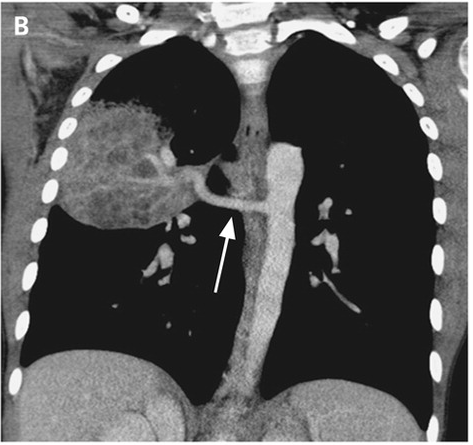

¼Ò¾Æ ³²È¯

fever¿Í chest painÀ¸·Î ÀÀ±Þ½Ç ³»¿ø.

Áø´Ü¸í°ú Ä¡·á ´äº¯ÁÖ¼¼¿ä.

weekly10 °áÇÙ¹× È£Èí±âÇÐȸ case ¿Í µ¿ÀÏÇÕ´Ï´Ù.